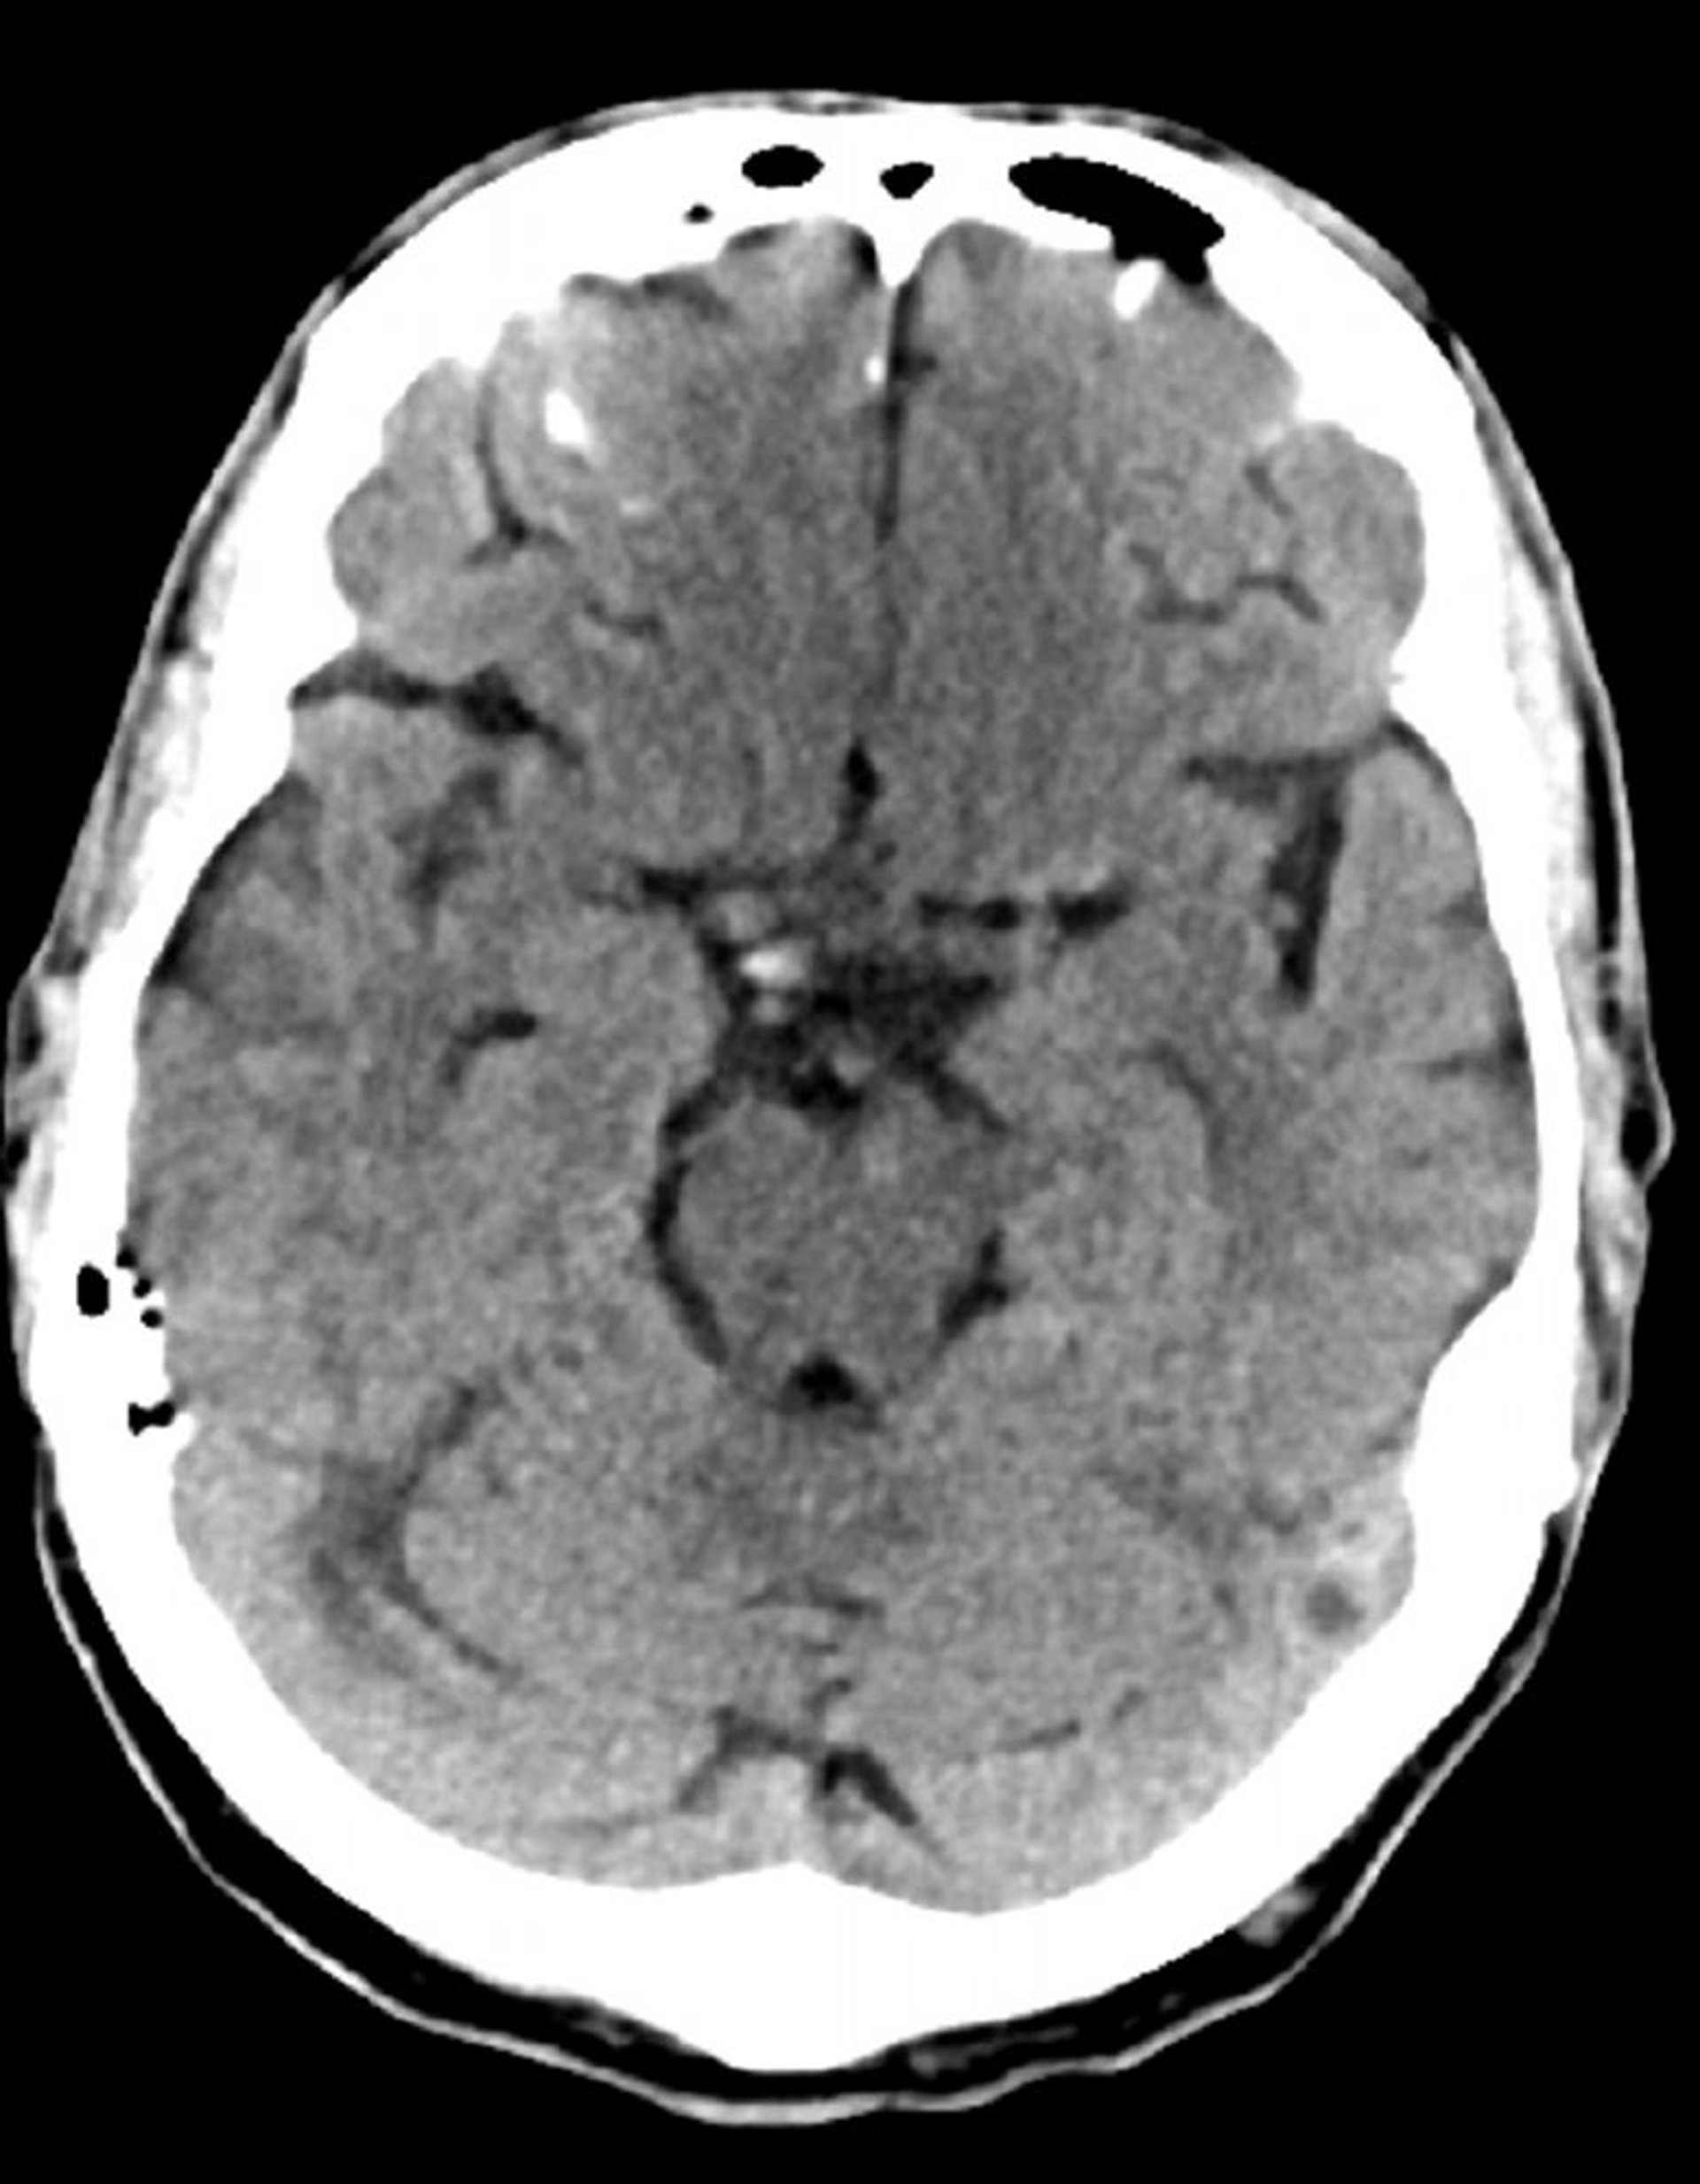

正常な頭部CT(成人,74歳)―スライド7

これは74歳成人の正常な頭部CT画像である。30歳の正常な頭部CT画像と比較すると,脳室および脳溝がより大きくなっている。これらの所見はこの年齢層では正常である。